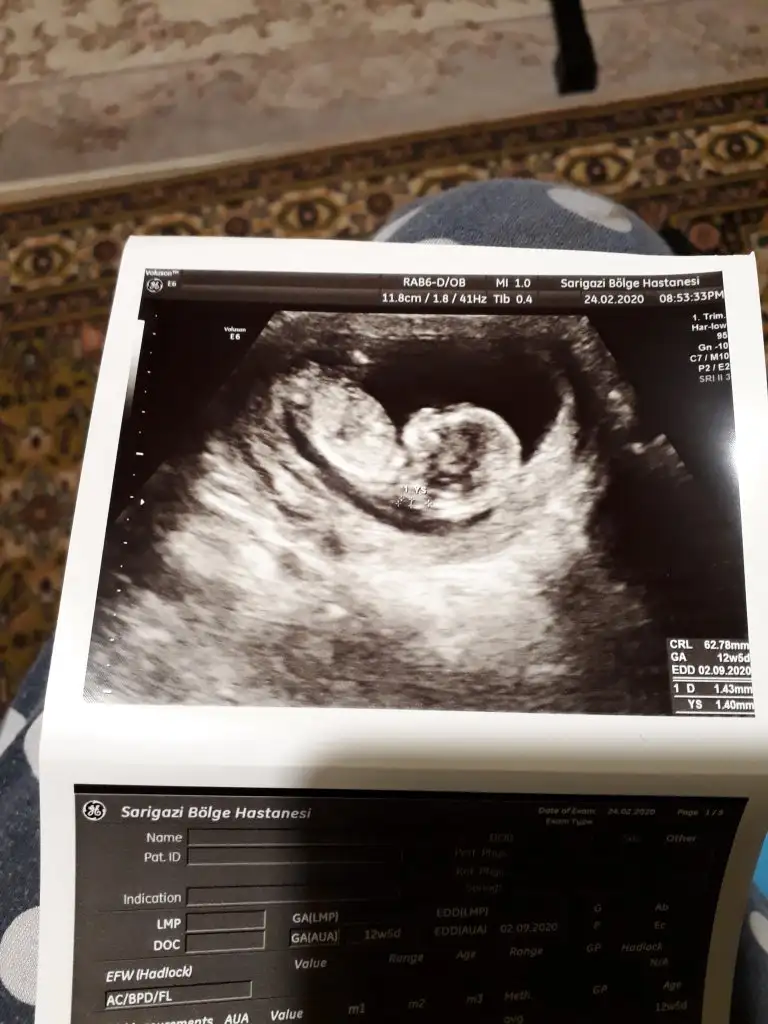

Dr + tam nuba denk getirmiş başka usg varmı12+4 banada yorumlarmisijizIkra meyra

Bu göre kız ama tutmayabilir tekrar usg olursa paylaşın .usteki 12+3 usg de kafa yapısı kız gibi ama nub göremiyorum .13+ usg olursa paylaşırsınızBaska yok![]()

Bu göre kız ama tutmayabilir tekrar usg olursa paylaşın .usteki 12+3 usg de kafa yapısı kız gibi ama nub göremiyorum .13+ usg olursa paylaşırsınız![]()